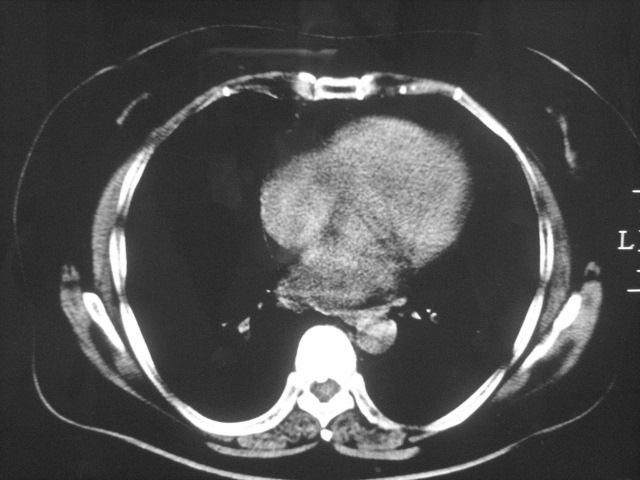

以下是引用清清楚楚在2007-8-28 7:13:00的发言:[br]右肺下叶可见斑片状高密度影,边缘模糊;右肺中叶内侧段及左肺舌段亦可见小斑片状模糊影。[br]考虑双肺感染,建议抗炎治疗后复查。

以下是引用天南地北在2007-8-27 23:49:00的发言:[br]右肺下叶可见斑片状高密度影,边缘模糊;右肺中叶内侧段及左肺舌段亦可见小斑片状模糊影。[br]考虑双肺感染,建议积极抗炎治疗后复查。

以下是引用天南地北在2007-8-27 23:49:00的发言:[br]右肺下叶可见斑片状高密度影,边缘模糊;右肺中叶内侧段及左肺舌段亦可见小斑片状模糊影。[br]考虑双肺感染,建议抗炎治疗后复查。

以下是引用难听在2007-8-28 13:17:00的发言:[br]右肺下叶背段支气管狭窄,是否可以考虑新生物伴阻塞性肺炎.请大家帮帮忙,这个病人是卫生局长的丈母娘.惹不起啊.